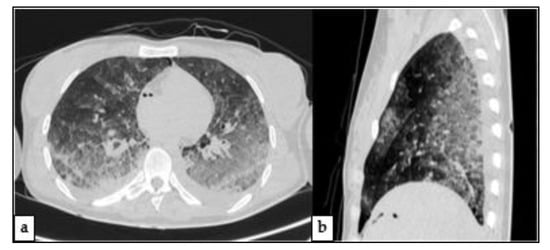

2.3. Post-Mortem Computed Tomography (PMCT)

2.4.3. Other Findings